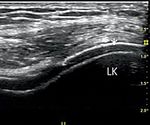

Abbildung 4: Potenzielles sonografisches Zeichen der    Abbildung 5: Röntgen linkes Kniegelenk – Verkalkung   Abbildung 6: Polarisationsmikroskop –

chen (roter Pfeil) [15]. LK = Laterale Kondyle

gewesen. Zum Zeitpunkt der Kniegelenksar-               alle zwei bis vier Wochen um 100 bis 200 mg           HCT durch einen Calcium-Antagonisten) und

thritis zeigte sich sonografisch eine deutliche         bis zum Erreichen des Serumharnsäure-Zielwer-         eliminierten dadurch einen häufig in der Praxis

lokale Ergussbildung, minimale synoviale Proli-         tes von < 6 mg/dl). Die Standarddosis beträgt         auftretenden Auslöser erhöhter Harnsäurewerte

ferationszeichen, keine spezifischen pathologi-         300 mg/die, die maximale Dosis bis 800 mg/die         und möglicher Gichtanfälle [8, 9, 10].

schen Knorpel-/Knochenstrukturen (zum Beispiel          [8, 9]. Weitere zugelassene harnsäuresenkende

Doppelkonturzeichen bei Gicht, Abbildung 4).            Medikamente sind das Urikostatikum Febuxostat         Der Patient war durch die eingeleiteten Therapie-